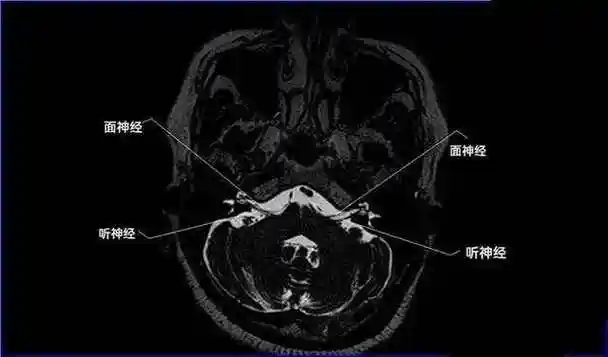

12对颅神经连续层面mri解剖